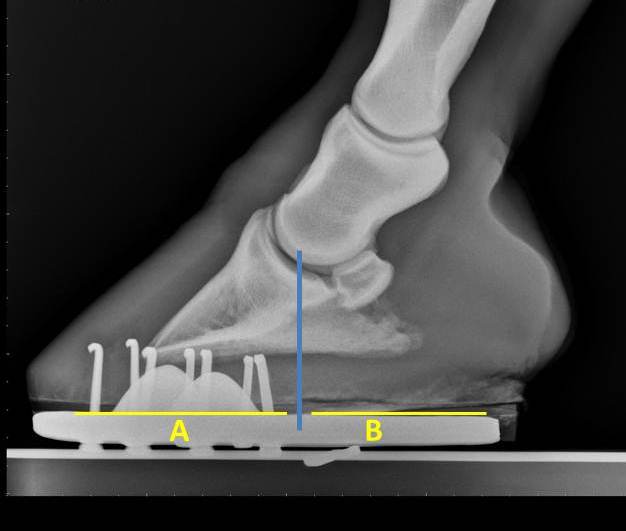

| Figure 1 |

The cause of the chronic dorsal displacement of the soft palate in this case is in part due to chronic inflammation of the soft palate (yellow arrow) and potentially an abnormal epiglottis (blue star). The epiglottis was not visualized in this exam and may require an oral endoscopy and skull radiographs to better determine if there is a structural problem with the epiglottis. Management of this condition involves treating with systemic anti-inflammatory medications and medicated throat wash. If the soft palate remains displaced, surgical consultation is recommended. Yet another example of the benefit of an endoscopic exam for a horses that suffer from coughing, exercise intolerance, or nasal discharge.